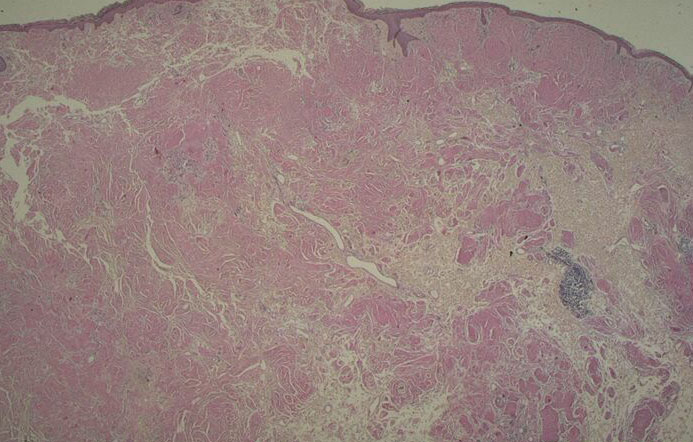

Nodular amyloid =الداء النشواني العقيدي